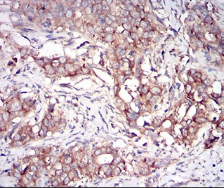

IHC    1/100 - 1/500